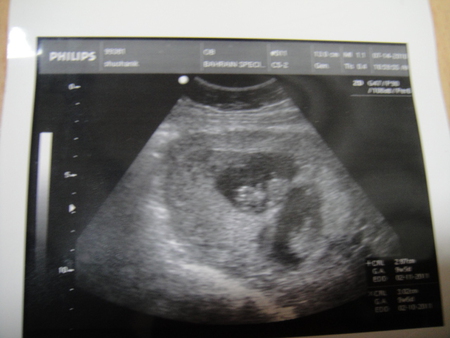

Узи 6 недель нет сердцебиения

Узи 6 недель нет сердцебиения 119 фотографий